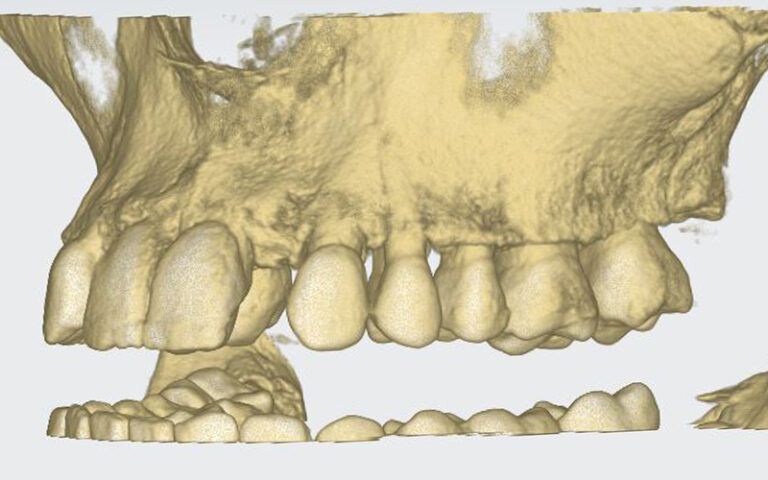

Patient’s initial CT scan after orthodontic treatment Patient’s initial CT scan after orthodontic treatment Patient’s initial CT scan after orthodontic treatment

STL images for planning STL images for planning STL images for planning

After this time a CBCT was taken of the maxilla to start planning the surgery for the placement of two implants in positions 12 and 22. During the analysis of the x-ray images, as the measurements indicate, it was observed that the mesio-distal space between 11-13 and 21-23 was limited, which would impede the placement of two standard implants with a diameter of 3.3 mm.